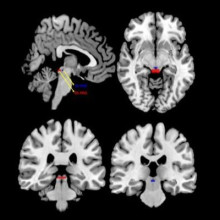

The research team is hoping to recruit approximately 60 people to take part in the DBR study.  Participants will undergo a psychological interview and an MRI, then eight sessions of treatments. Following those sessions, participants will have another interview and MRI to assess if any positive changes were made within the neurological networks and/or in psychological systems.